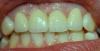

N@t@ly Опубликовано 5 июля, 2010 Автор Поделиться Опубликовано 5 июля, 2010 фотографию дайте пожалуйста. Вот фотография Ссылка на комментарий

N@t@ly Опубликовано 5 июля, 2010 Автор Поделиться Опубликовано 5 июля, 2010 в этом случае проще поднимать арку одного резца - только она выбивается из всей гаммы 4 зубов.над тремя зубами арку уже не опустишь. поздно. обточены. что-то не поняла... не очень хорошо видно на фото, но десна "провалилась", из-за этого зуб как-бы выступает из-под нее. Может описала не по-человечьи, но как-то так Ссылка на комментарий

Bier Опубликовано 6 июля, 2010 Поделиться Опубликовано 6 июля, 2010 самый простой способ - поднять десну на левой единице до уровня правой. О чем вам и написал Fury Ссылка на комментарий